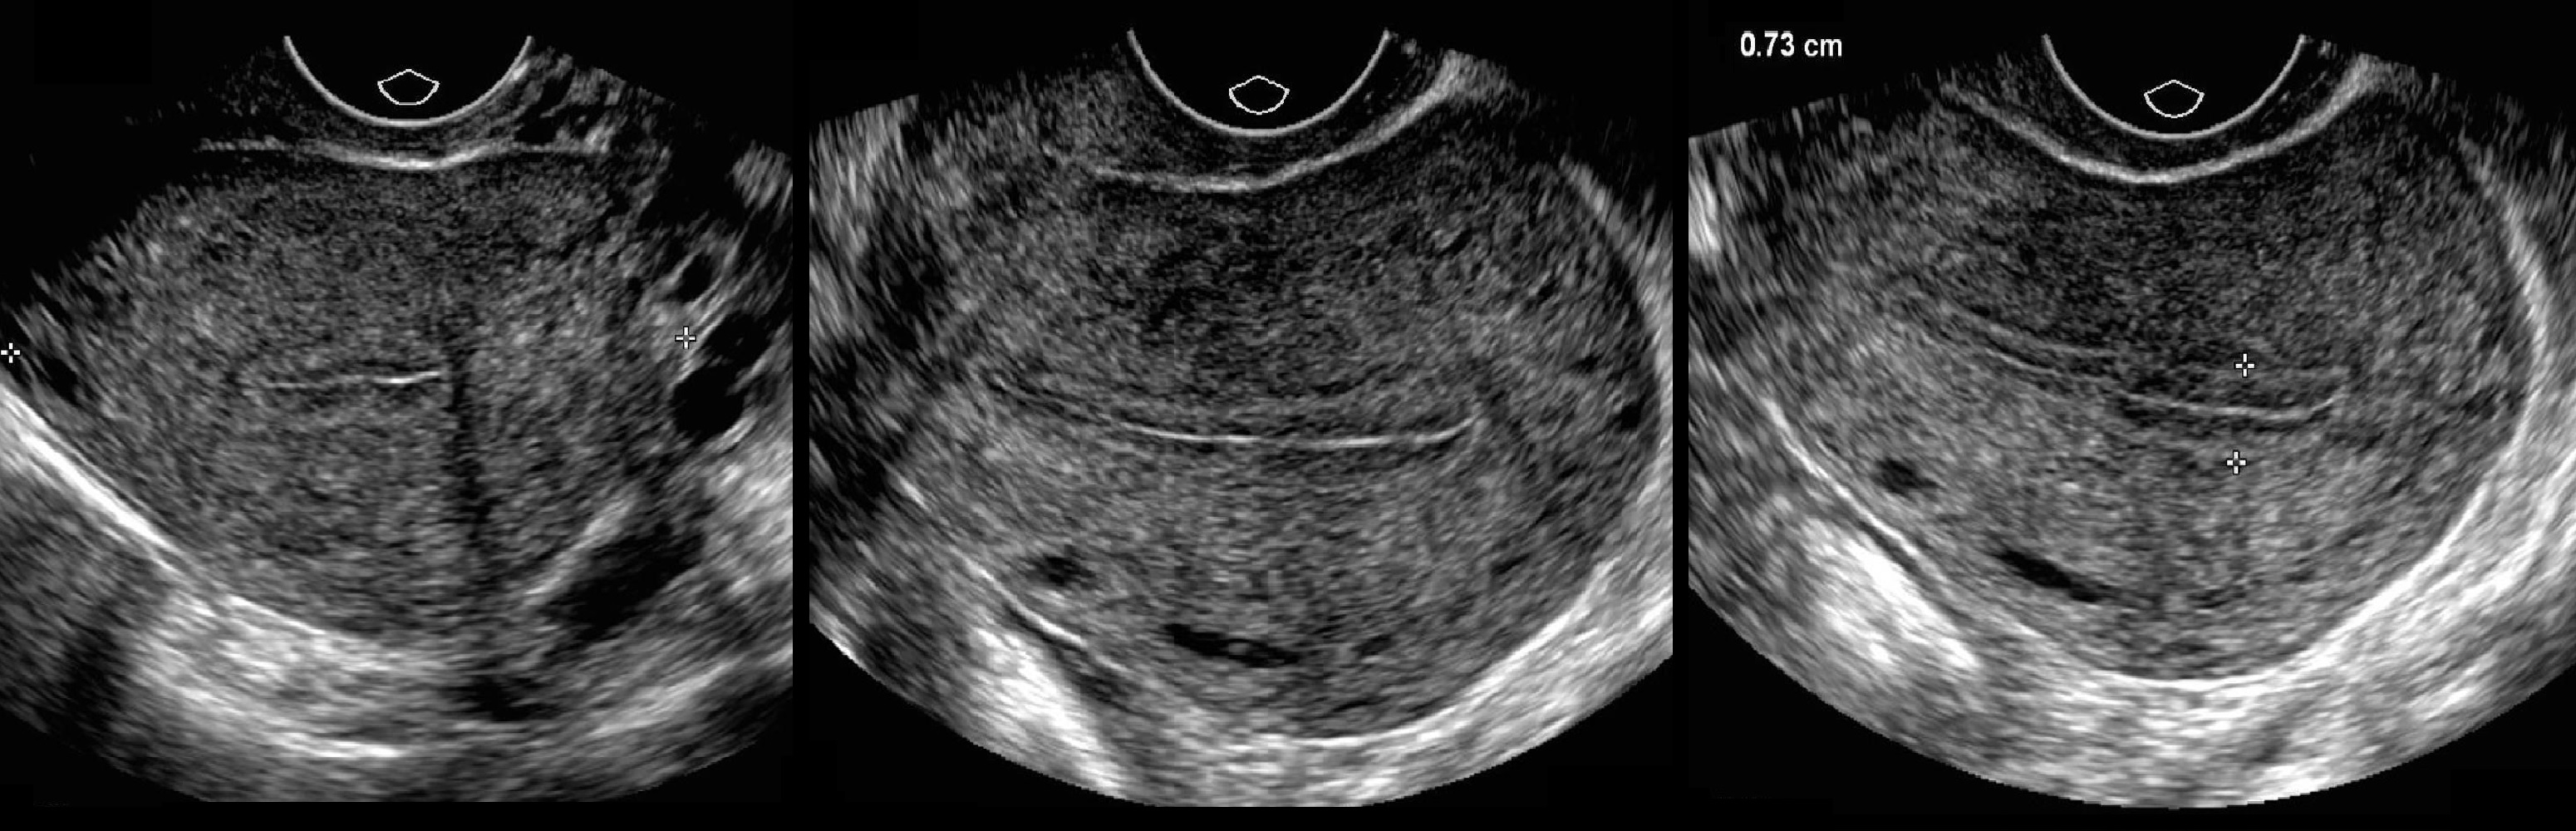

Медицинская диагностика: Гиперплазия эндометрия на УЗИ